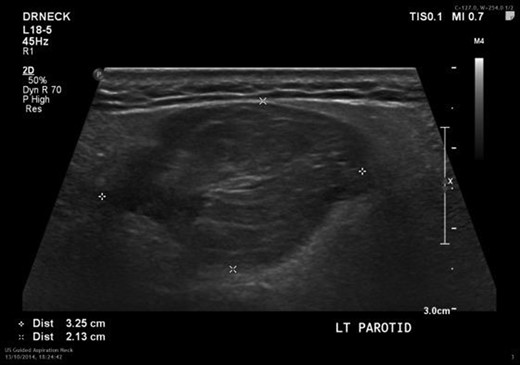

An US scan showed a well-defined non-vascular hypoechoic lesion in the left superficial parotid lobe measuring 3.2 × 2.2 × 2.6 cm (Fig. 2). The corresponding fine needle aspirate cytology was inconclusive. MRI showed high signal intensity on T1-weighted images (Fig. 3) and a branching vessel-like central structure traversing the lesion. These results were consistent with a lipomatous lesion. Surgical removal was performed via an extra-capsular dissection with facial nerve preservation. The tumour comprised of a well-circumscribed, soft yellow, fatty mass covered in a thin fibrous capsule (Fig. 4). Postoperative facial nerve function was normal with transient altered sensation to the ear lobe. Histopathology showed a homogenous proliferation of mature adipocytes, confirming the diagnosis of a lipoma. On 6-month review, there are no signs of recurrence.

Ultrasound of the left parotid gland showing a well-circumscribed hypoechoic lesion.